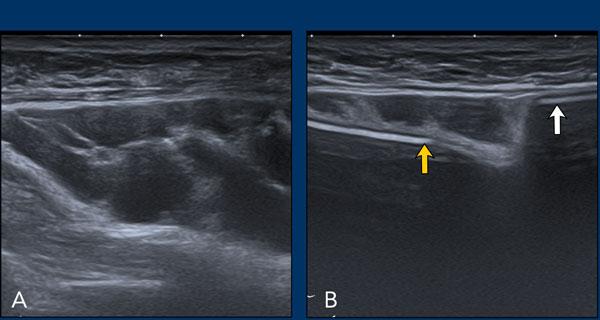

Hình ảnh

A. Túi độn nước muối sinh lý có van bơm.

B. Màng ngăn (diaphragm) đối xứng, bờ rõ nét, nằm ở trung tâm, có thể bắt chước hình ảnh bất thường của vỏ bọc.

C. Loại bình chứa khác.

A. Không còn nhìn thấy vỏ bọc xung quanh bề mặt túi độn. Nội dung bên trong hoàn toàn không đồng nhất và thoái hóa.

B. Vỏ bọc bị xẹp (mũi tên vàng) và không đi theo phức hợp vỏ bọc-bao xơ bên ngoài (mũi tên trắng).

Có một khối tập hợp không đồng nhất chứa Silicone nằm giữa vỏ bọc và bao xơ.